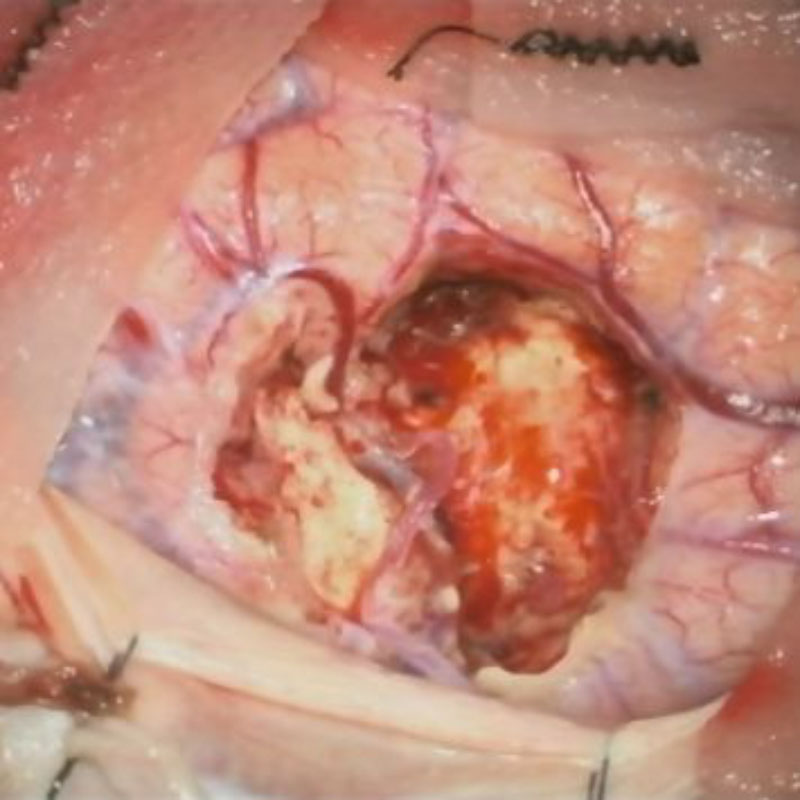

694

'25年11月

90代

頭蓋咽頭腫

頭蓋内腫瘍摘出術

No.’25_96 摘出 前

No.’25_96  摘出 中

No.’25_96 摘出 後